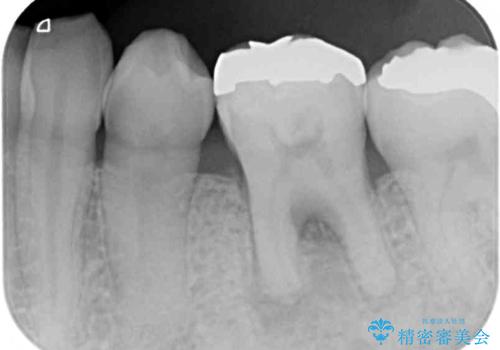

- 上顎大臼歯が食事の度に痛みを感じるとのことで来院された患者様です。

レントゲン写真などで診査を行ったところ、神経組織が壊死し、根尖部周辺の骨に炎症が認められました。

まずは根管治療を行い、症状が消退したことを確認してオールセラミッククラウンにて補綴治療を行うこととしました。